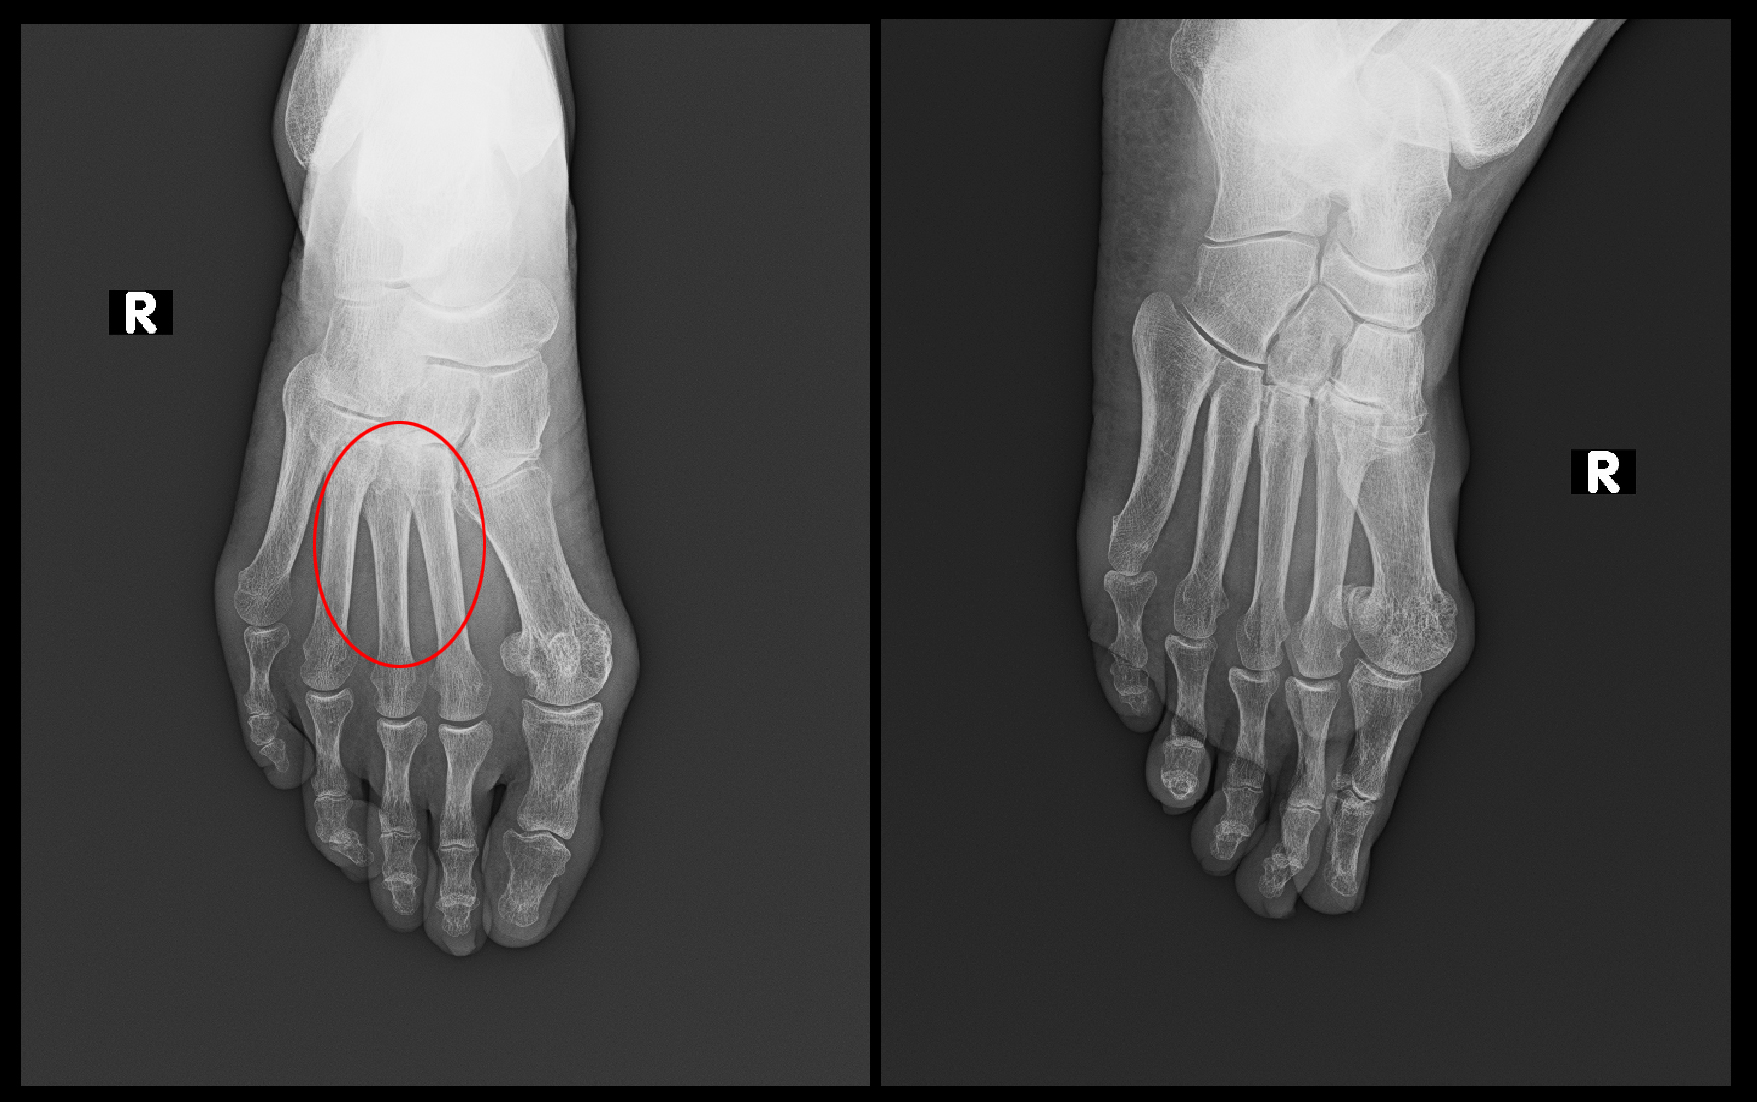

次の症例は74才の女性で、北海道在住の息子さんのところに長期出かけていて、令和7年5月7日玄関で転倒し左手関節と左足関節の軽微な骨折を受傷され、地区の病院の整形外科に通院していたのに3か月半経過しても(当初の受傷部位=左足関節と異なる)左足背部痛と左母指・示指(人差指)の痛みが続くためにリハビリを続けていた患者さんとなります。8月24日に当院を受診されました。

74才女 Xp1.jpgレントゲン像からすれば、左手関節も左足関節もどこが骨折だったの?というほどの軽微な骨折で普通の治療であれば2か月も経てば問題なく治癒していていいような骨折でした。左足部の骨は異常を認めません。

私の診断では左母指・示指痛は骨折とは直接関係のない腱鞘炎であり、左足背部痛は左第2~第4足趾MP関節に圧痛を認め、関節炎を疑いました。(※部位別の診療例の提示“足” 「足指の痛み その1」を参照してください。)左足部痛に対してはMRI検査を実施しています。また、患者さんはリハビリで左手指を動かされると、とても痛かったと言っていましたが、当院での腱鞘炎の1回の局所注射で治癒しています。